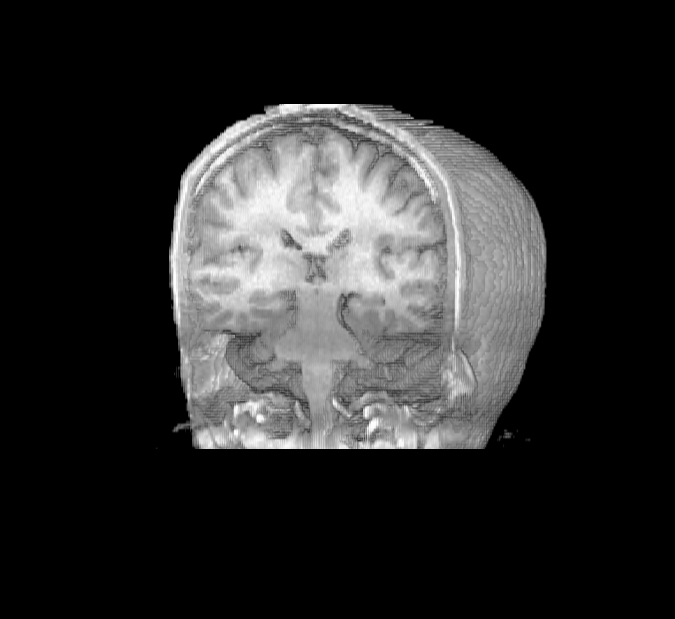

Magnetic resonance imaging (MRI)

Note:

MRI

- Uses rotating magnets to generate image

- Non-invasive

- Can view images from any angle

- Resolution can be less than 1 mm

- Can be adapted to do functional MRI imaging

fyi: The MRI image is J. Ackman's brain from 2009!